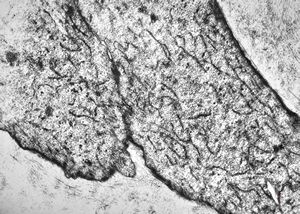

F,32y. | transversally sectioned skeletal muscle cell

mouse skeletal muscle cell - transversal section